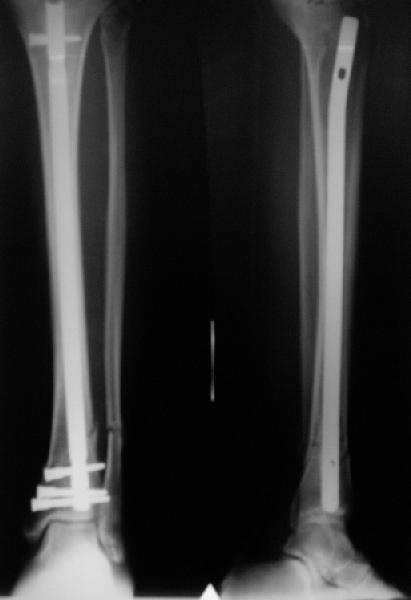

There are some more tricks which allow not to plate the fibula and provide good alignment and stability. A small wire distractor can provide alignment and restore length of both tibia and

fibula. Angular stability of the tibia is provided by insertion of more than two conventional medial-lateral locking screws. To maintain the position of the fibula perQ insertion of a single position screw often could be enough. I bet the articles didn't analyze the options.

A typical case is attached, also an image with intra-op reduction obtained by a small wire distractor, in the moment of insertion a Poller wire in AP direction. Fixation by a SIGN nail. Despite the fibula was not fixed healing was obtained with the unchanged alignment.

[ Ответить ]